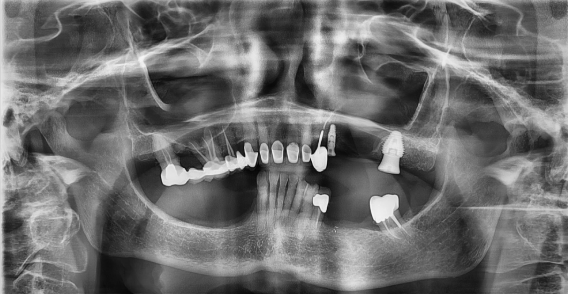

Patient se présente avec fracture de la 27 pilier de bridge.

Objectif : préservation osseuse alvéolaire résiduelle sur un site présentant une faible quantité d’os et le sinus en proximité immédiate.